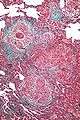

| High magnification photomicrograph of a lung biopsy taken showing chronic hypersensitivity pneumonitis (H&E), showing mild expansion of the alveolar septa (interstitium) by lymphocytes. A multinucleated giant cell, seen within the interstitium to the right of the picture halfway down, is an important clue to the correct diagnosis. | |

Lung biopsy

Lung biopsies can be diagnostic in cases of chronic hypersensitivity pneumonitis, or may help to suggest the diagnosis and trigger or intensify the search for an allergen. The main feature of chronic hypersensitivity pneumonitis on lung biopsies is expansion of the interstitium by lymphocytes accompanied by an occasional multinucleated giant cell or loose granuloma.[8][9]